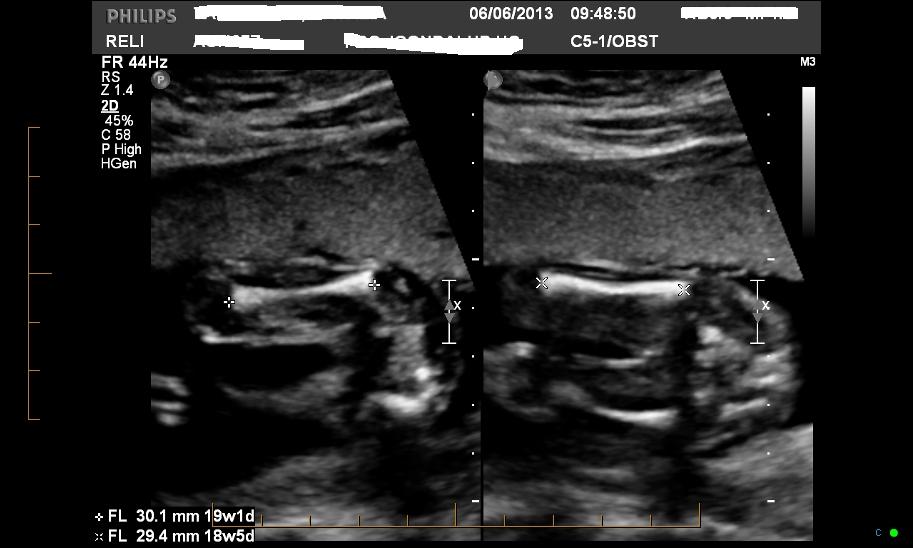

Very new here. Had my 20 week scan yesterday and was wondering if you could possibly tell the gender? I don't even know if these shots would be clear enought either.